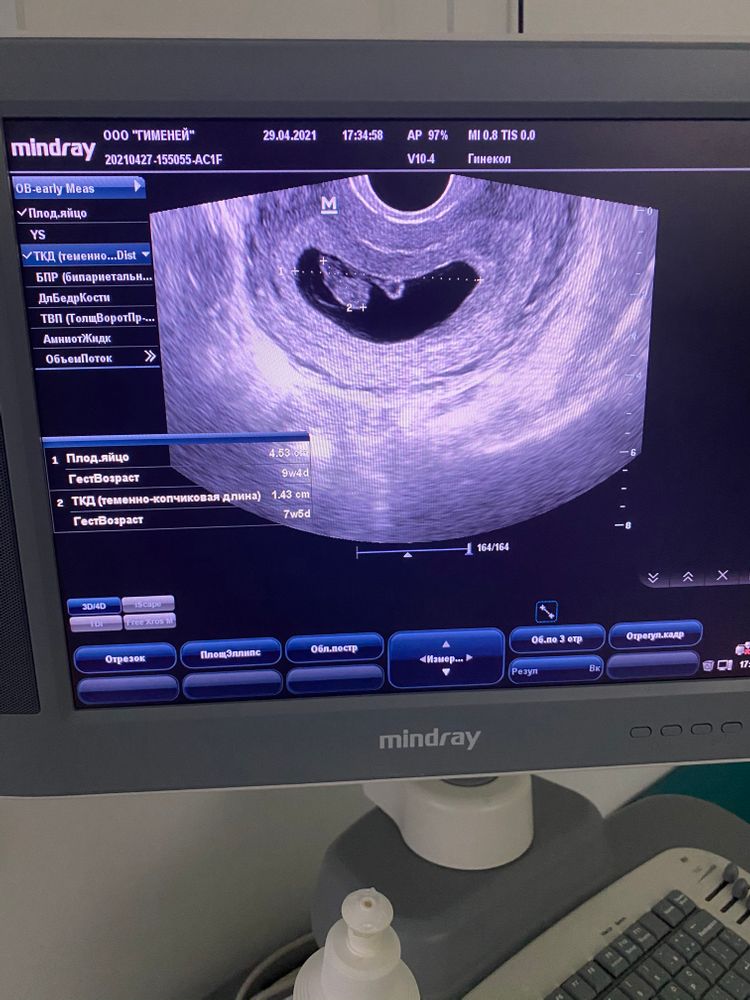

Узи 8+1

Наши будни, наши неделькиДелала ещё в 6+3, решила посмотреть динамику, и у нас все хорошо ☺️

КТР 1.43

ПЯ 4.53